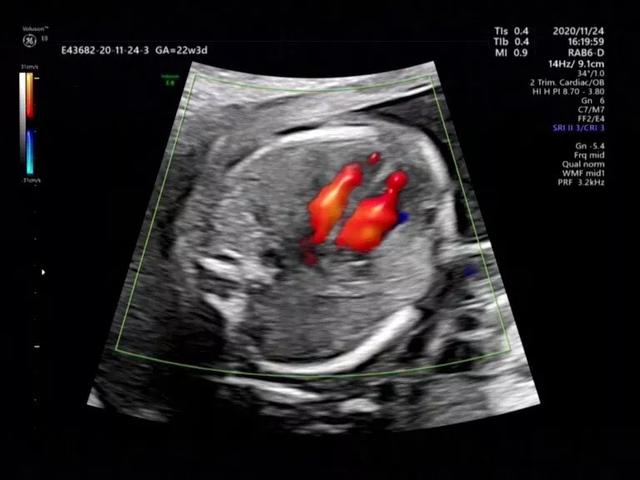

评估胎盘、宫颈、婴儿活动度、羊水量等。并测量脐动脉血流来间接判断宝宝的营养供应,并评估是否有严重缺氧和宫内窘迫等。